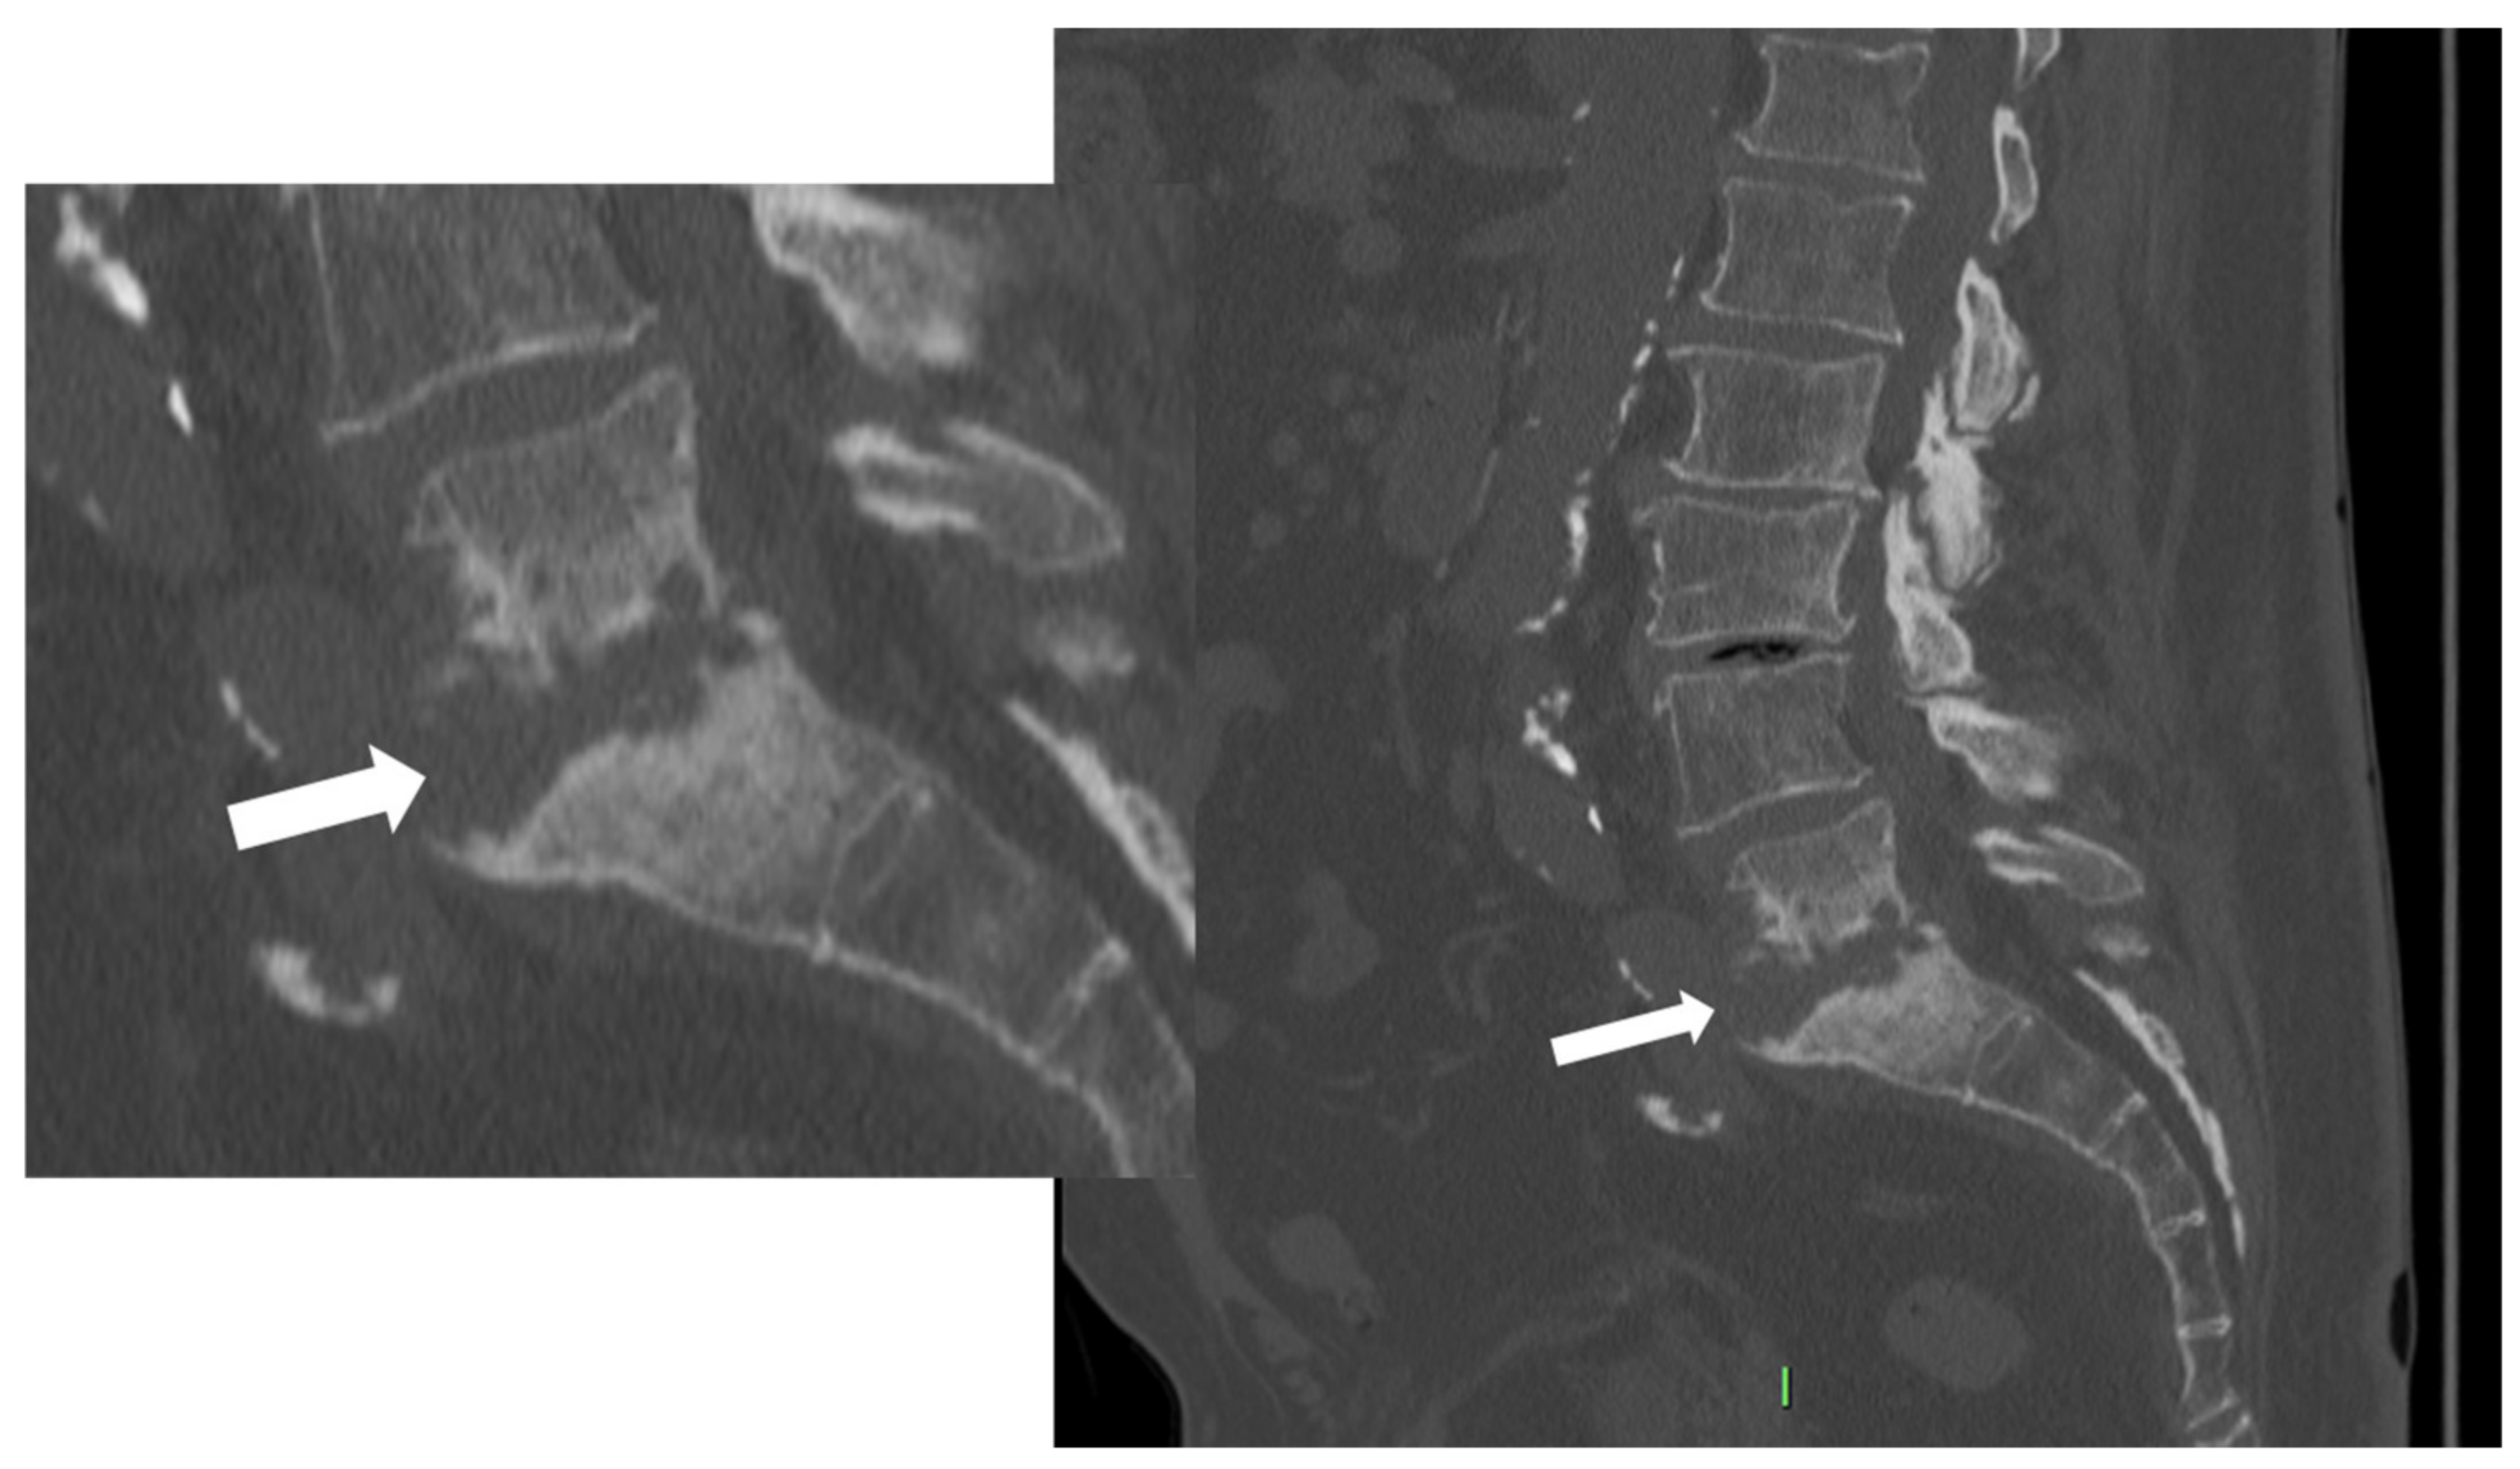

Figure 3. CT, sagittal reconstruction (magnification on the left), of a 77-year-old female with L5-S1 pyogenic spondylodiscitis characterized by thick endplates erosions (arrows).

As the infection progresses, CT may show soft tissue replacement of the bone. The involvement of the bone can result in erosive changes to the end plates (Figure 3).

Additionally, direct inoculation of the disk space might occur, involving the subjacent end plate and potentially leading to the collapse of the disk space [36,37].